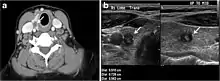

Fig. 4. A 45-year-old male patient presented with anterior mediastinal metastatic PTC lesions and occult primary on imaging. Histopathology examination of the resected thyroid gland revealed micro-foci of PTC; the largest, in the isthmus, measured 4 mm. a transverse greyscale ultrasound of the thyroid demonstrates homogeneous gland with normal echogenicity and size. No focal lesion or micro-calcifications. b Non-enhanced CT scan obtained as part of PET/CT examination shows a heterogeneous, large, relatively dense anterior mediastinal mass (white arrow) with peripheral calcification (arrowheads). Thyroid gland has normal CT appearance with no abnormal FDG uptake (not shown).[1]